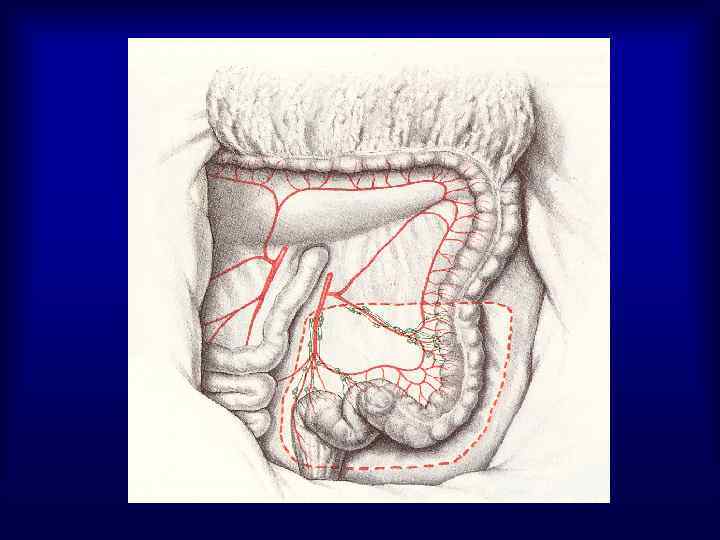

Виды операций при раке прямой кишки 1. Брюшно-промежностная экстирпация прямой кишки (25%) 2. Чрезбрюшная (передняя) резекция прямой кишки (50%) 3. Брюшно-анальная резекция прямой кишки (25%) 4. Операция Hartmann (5%) 5. Экономные операции – при размерах опухоли 1 -4 см, расположенных на расстоянии 3 -10 см от заднего прохода (трансанальное иссечение скальпелем, электроножом, лазером, криодеструкция, эндоскопическая коагуляция)

Хирургическое лечение рака прямой кишки 1. 2. 3. 4. Чрезбрюшная резекция прямой кишки выполняется при локализации опухоли не ниже 8 см от анального кольца Брюшно-анальная резекция прямой кишки с демукозацией слизистой анального канала и формированием колоанального анастомоза могут осуществляться у больных с локализацией опухоли на расстоянии 6 см и выше от аноректальной линии Операция Hartmann выполняется у пациентов пожилого и старческого возраста, с сопутствующей патологией, при наличии непроходимости, распадающейся опухоли, отдаленных метастазов с локализацией процесса не ниже 8 см от ануса Брюшно-промежностная экстирпация ПК выполняется при локализации опухоли в анальном канале, при нижнеампулярных раках, а также при возникновении интраоперационных осложнений